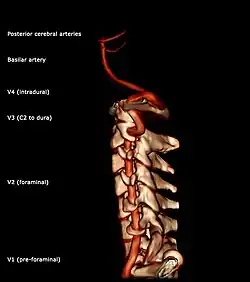

• Segments of vertebral artery lateral projection

The fourth (intradural or intracranial) part pierces the dura mater and inclines medially to the front of the medulla oblongata; it is placed between the hypoglossal nerve and the anterior root of the first cervical nerve and beneath the first digitation of the ligamentum denticulatum. At the lower border of the pons, it unites with the vessel of the opposite side to form the basilar artery.

The vertebral artery may be divided into four parts:

• The first (preforaminal) part runs upward and backward between the anterior scalene and the longus colli muscles. In front of it are the internal jugular and vertebral veins, and is crossed by the inferior thyroid artery; the left vertebral is also crossed by the thoracic duct. Behind it are the transverse process of the seventh cervical vertebra, the sympathetic trunk and its inferior cervical ganglion

• The second (foraminal) part runs upward through the transverse foramina of the C6 to C2 vertebrae, and is surrounded by branches from the inferior cervical sympathetic ganglion and by a plexus of veins which unite to form the vertebral vein at the lower part of the neck. It is situated in front of the trunks of the cervical nerves, and pursues an almost vertical course as far as the transverse process of the axis.

• The third (extradural or atlantic) part issues from the C2 foramen transversarium on the medial side of the Rectus capitis lateralis. It is further subdivided into the vertical part V3v passing vertically upwards, crossing the C2 root and entering the foramen transversarium of C1, and the horizontal part V3h, curving medially and posteriorly behind the superior articular process of the atlas, the anterior ramus of the first cervical nerve being on its medial side; it then lies in the groove on the upper surface of the posterior arch of the atlas, and enters the vertebral canal by passing beneath the posterior atlantoöccipital membrane. This part of the artery is covered by the Semispinalis capitis and is contained in the suboccipital triangle—a triangular space bounded by the Rectus capitis posterior major, the Obliquus superior, and the Obliquus inferior. The first cervical or suboccipital nerve lies between the artery and the posterior arch of the atlas.